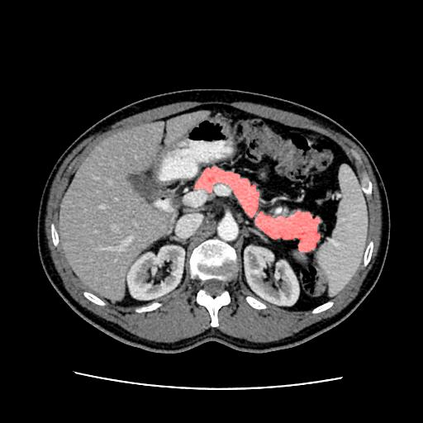

In this paper, we adopt 3D Convolutional Neural Networks to segment volumetric medical images. Although deep neural networks have been proven to be very effective on many 2D vision tasks, it is still challenging to apply them to 3D tasks due to the limited amount of annotated 3D data and limited computational resources. We propose a novel 3D-based coarse-to-fine framework to effectively and efficiently tackle these challenges. The proposed 3D-based framework outperforms the 2D counterpart to a large margin since it can leverage the rich spatial infor- mation along all three axes. We conduct experiments on two datasets which include healthy and pathological pancreases respectively, and achieve the current state-of-the-art in terms of Dice-S{\o}rensen Coefficient (DSC). On the NIH pancreas segmentation dataset, we outperform the previous best by an average of over 2%, and the worst case is improved by 7% to reach almost 70%, which indicates the reliability of our framework in clinical applications.